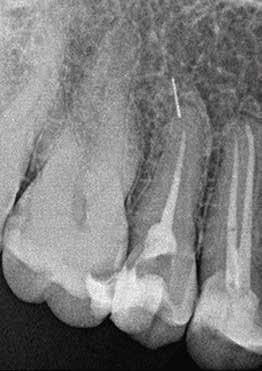

Esetbemutatás (1.)

Egy 63 éves páciens korábban már kezelt bal alsó első nagyőrlőfogából (3.6) eredő mérsékelt fájdalom miatt kereste fel rendelőnket. A kórtörténetében panasza szempontjából releváns információ nem szerepelt. Az elkészült CBCT-felvételen a korábbi kezelések során észre nem vett, jelenleg feltáratlan meziobuccalis csatornát, valamint a mezialis és distalis gyökerek körül kialakult periapicalis elváltozást, és ezt a léziót borító intakt buccalis corticalis csontlemezt láttunk.

A fog revideálását és újbóli gyökértömését két ülésben végeztük el. A régi gyökértömés eltávolítását, valamint mindhárom gyökércsatorna megmunkálását és fertőtlenítését követően kalcium-hidroxid alapú gyógyszeres zárást helyeztünk a gyökércsatornákba. A gyökértömés egy héttel később került behelyezésre. A páciens panaszai két hónap elteltével sem szűntek.

Klinikai vizsgálat során vertikális kopogtatási érzékenységet jelzett. A fog körül mérhető szondázási mélység és a fogmobilitás fiziológiás volt. A CBCT-felvételen nem észleltünk a csontos regeneráció megindulására utaló jeleket (1. a–c. ábrák). A korábban gyökérkezelt, gyökértömött és revideált 3.6-os fog esetében az alábbi diagnózis került felállításra: periodontitis periapicalis symptomatica. A panaszokat okozó fog további ellátása során navigált endodonciai mikrosebészetet kívántunk alkalmazni. Az alsó állcsontról intraorális szkent (TRIOS, 3Shape) készítettünk, és a felszíni topográfiát tartalmazó STL fájlt, valamint a CBCT-felvétel készítése során nyert DICOM fájlokat a Blue Sky Bio szoftver segítségével egyesítettük. A sebészi sablon megtervezésére az így kapott háromdimenziós képet használtuk. A sablon kialakítása során arra törekedtünk, hogy a sablon egyértelműen meghatározza a gyökércsúcsi terület eléréséhez szükséges csontablak határait (1. d. ábra)

A beavatkozás során helyi érzéstelenítésben teljes vastagságú mucoperiostealis lebenyt képeztünk, és a sablon segítségével bejelöltük a preparálandó csontablak határait. Az ablak széleinek megfelelően Piezotome CUBE LED kézi-darabbal (ACTEON) a kortikális teljes vastagságában vágást ejtettünk, majd az így kapott csontlemezt (ablakot) eltávolítottuk (1. e–h. ábra), és ezt követően steril fiziológiás sóoldatba helyeztük. A rezekció elvégzését követően (1. i. ábra) a mezialis csatornákat ultrahangos eszközök segítségével (NSK) retrográd irányból preparáltuk, majd az így kialakított mélyedésbe retrográd gyökértömést készítettünk. A tömés anyagául az EndoSequence BC RRM Fast Set Putty-t (Brasseler) választottuk. A tömés elkészítését követően a csontablakot visszaillesztettük, és a stabilizálása érdekében a vágásoknak megfelelően kialakult résekbe kollagén szivacsokat (Collagen Tape, Zimmer Biomet) helyeztünk (1. j-k. ábra). A lebenyt 6/0-s Prolene varratokkal (Corpaul) rögzítettük.

A kétéves kontroll során elvégzett klinikai és radiológiai vizsgálat (CBCT-felvétel) a periapicalis elváltozások megszűnését és a corticalis csontállomány tünet- és szövődménymentes gyógyulását